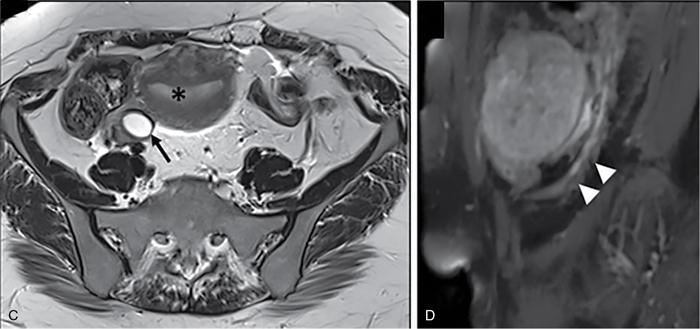

Suriyaprakash Nagarajan, Rupa Renganathan, Suhasini Balasubramaniam, Anupama Chandrasekharan, Kumarsampath Sumeena OVARIAN CYST VERSUS BLADDER Cystic lesions are common in female pelvis and mostly they originate from ovary. Ovarian cysts can arise from epithelial, stromal or germ cell components and can be benign or malignant cystic lesions. Pelvic Ultrasonography (USG) is the preferred imaging modality for evaluation of adnexal cystic lesions. Large simple ovarian cyst appears unilocular, anechoic with thin smooth walls. Such large simple cysts are confused with distended bladder. Distended bladder is a condition in which the urinary bladder is full and the patient is unable to void completely causing abdominal discomfort and pain. Distended bladder can be due to obstruction to passage of urine, neurological disorder or spastic sphincter. Differential diagnosis of cystic lesions in pelvis can be intraperitoneal, extraperitoneal and both intraperitoneal and extraperitoneal. Cystic lesions of intraperitoneal origin includes peritoneal inclusion cyst, paraovarian cyst, mucocele of appendix and hydrosalpinx. It is important to differentiate large simple ovarian cyst and distended bladder when patient presents with lower abdomen pain and the patient’s clinical history helps to make an accurate diagnosis (Table 11.4.1.1). UTERINE VERSUS EXTRAUTERINE MASS Ultrasound is usually the initial imaging modality for the pelvic mass. When USG findings are indeterminate to ascertain the organ of origin and to characterize, the next imaging modality is MRI due to its superior soft tissue resolution and multiplanar imaging capability (Figs. 11.4.2.1 and 11.4.2.2). Signs are demonstrated in Figs. 11.4.2.3 to 11.4.2.6. The sequences used in MRI pelvis are conventional T2WI in all three planes and T1WI in single plane. The problem-solving sequences are oblique coronal and oblique axial T2 along and perpendicular to the long axis of uterus in sagittal localizer. It can identify the organ of origin. Other sequences like T1 fat sat, diffusion-weighted imaging (DWI) and dynamic contrast T1WI with fat sat and subtracted images help to characterize the lesion further. BLADDER MASS VERSUS PROSTATE MASS Irregular mass lesions in the bladder neck are termed as ‘Bladder occupying lesions’. It is often difficult to determine whether the origin of these lesions is the bladder or the prostate gland. Transabdominal Ultrasound with colour Doppler studies and CT imaging do not usually delineate the origin of the lesions. The following features may aid in the differentiation (Table 11.4.3.1): History Painless haematuria Usually asymptomatic Investigations TAS, TRUS, MRI, Cystoscopy-guided biopsy PSA, DRE, TRUS, MRI, TRUS-guided biopsy At what point is the cross over between the two lesions T4 bladder cancer invading the prostate Aggressive prostate cancer protruding into the bladder Epicenter of the lesion Within the bladder Within the prostate gland Central necrosis in the mass Not commonly seen Seen in sarcomas IVU/CT urography Additional lesions in the urinary tract suggest that the bladder occupying mass in the bladder neck is of bladder-origin Prostate masses do not commonly cause masses in the urinary tract except for the very rare metastasis Virtual cystoscopy Additional lesions in the bladder wall and dome suggest that the bladder occupying mass in the bladder neck is of bladder-origin MRI T2 hypointensity Bladder masses are usually T2 hyperintense Seen in adenocarcinomas MRI T2 hyperintensity Bladder masses are usually T2 hyperintense Urothelial tumours infiltrating the prostate, neuroendocrine masses MRI T1 and T2 hyperintensity Bladder masses are usually T1 hypointense and T2 hyperintense Mucinous adenocarcinoma MRS Elevated choline values are seen in highly cellular masses Elevated choline:citrate ratio in prostate malignancies No significant finding in mucinous adenocarcinoma DWI Diffusion restriction is seen in malignant bladder masses No restriction in mucinous adenocarcinoma BPH versus bladder mass Exophytic BPH has signal intensities and appearance similar to and is contiguous with BPH within the gland OVARIAN MASS VERSUS PARAOVARIAN MASS Ultrasonography (USG) is the primary imaging modality in patients presenting with pelvic symptoms. Transvaginal, transabdominal or both should be performed in evaluation of such patients to differentiate ovarian and nonovarian origin of the lesions. Ovarian lesions can be a simple ovarian cyst, complex cyst with septations and solid components or a solid mass. Paraovarian lesions are remnants of the Wolffian duct in the mesosalpinx along fallopian tube or the ovaries and do not arise from the ovary. Paraovarian cysts are classified based on their site of origin into paratubal mesosalpingeal cysts, hydatid cysts of Morgagni, paraovarian cystadenoma and subserosal cysts. Differentiation of ovarian and paraovarian lesion poses significant diagnostic challenge. Both Computed tomography (CT) and Magnetic resonance imaging (MRI) are essential problem-solving tool in determining the site of origin of a pelvic mass. The first step in pelvic mass evaluation is to find out if it is ovarian or nonovarian in origin. Characterization of paraovarian or ovarian lesions is of utmost importance in order to optimize therapeutic procedures and it influences patients management (Figs. 11.4.4.1 and 11.4.4.2). Findings such as ovarian vascular pedicle sign, claw sign, bird beak sign and visualization of normal ovary helps to differentiate between ovarian and paraovarian lesions. Subsequently ovarian lesions should be categorized into benign, indeterminate and malignant masses (Table 11.4.4.1).